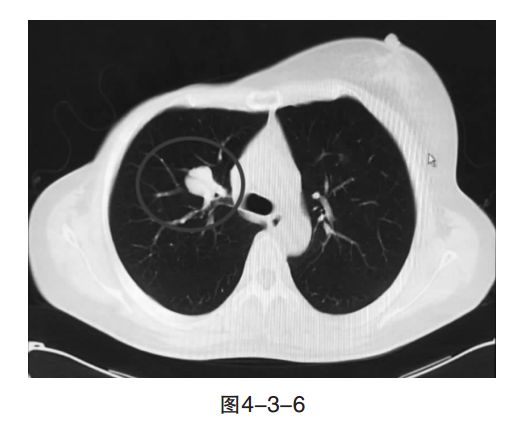

病情变化:2017年1月,复查胸CT发现,右肺上叶支气管旁结节较前增大,以及疗效增大的SD。2017年2月,将依维莫司增量至10mg,继续氟维司群治疗。2017年3月,复查右肺气管旁结节较前增大(图4-3-6),疗效为PD。

肿瘤内科专家点评

此处持续增大的病灶是既往穿刺确认乳腺癌来源的病灶。目前,患者内分泌治疗选用氟维司群联合依维莫司继发耐药,但获益时间较长(PFS=30个月)。此时,肿瘤负荷仍不大,无明显症状,下一步治疗仍可考虑以内分泌治疗为主。